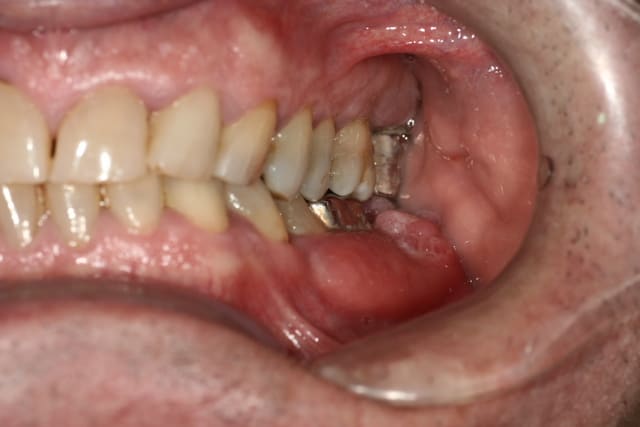

Présent depuis 1 mois, douloureux à la palpation en lingual, chaud et dépressible.

Pas de douleurs.

Il n'y aurait pas une lésion osseuse juste sous ces bourgeons???

Ca fait quand meme pas très bénin, non?

c'est moche mais c est pas ulcéré je pense pas que se soit malin ce truc

pas malin, c'est pas sur.

J'ai vu une fois un carcinome verruqueux qui avait cet aspect exterieur et le meme aspect radio.

comme pepe54 , envoi rapide en service hospitalier, je ne mettrais pas 10 kopeks sur un truc bénin.